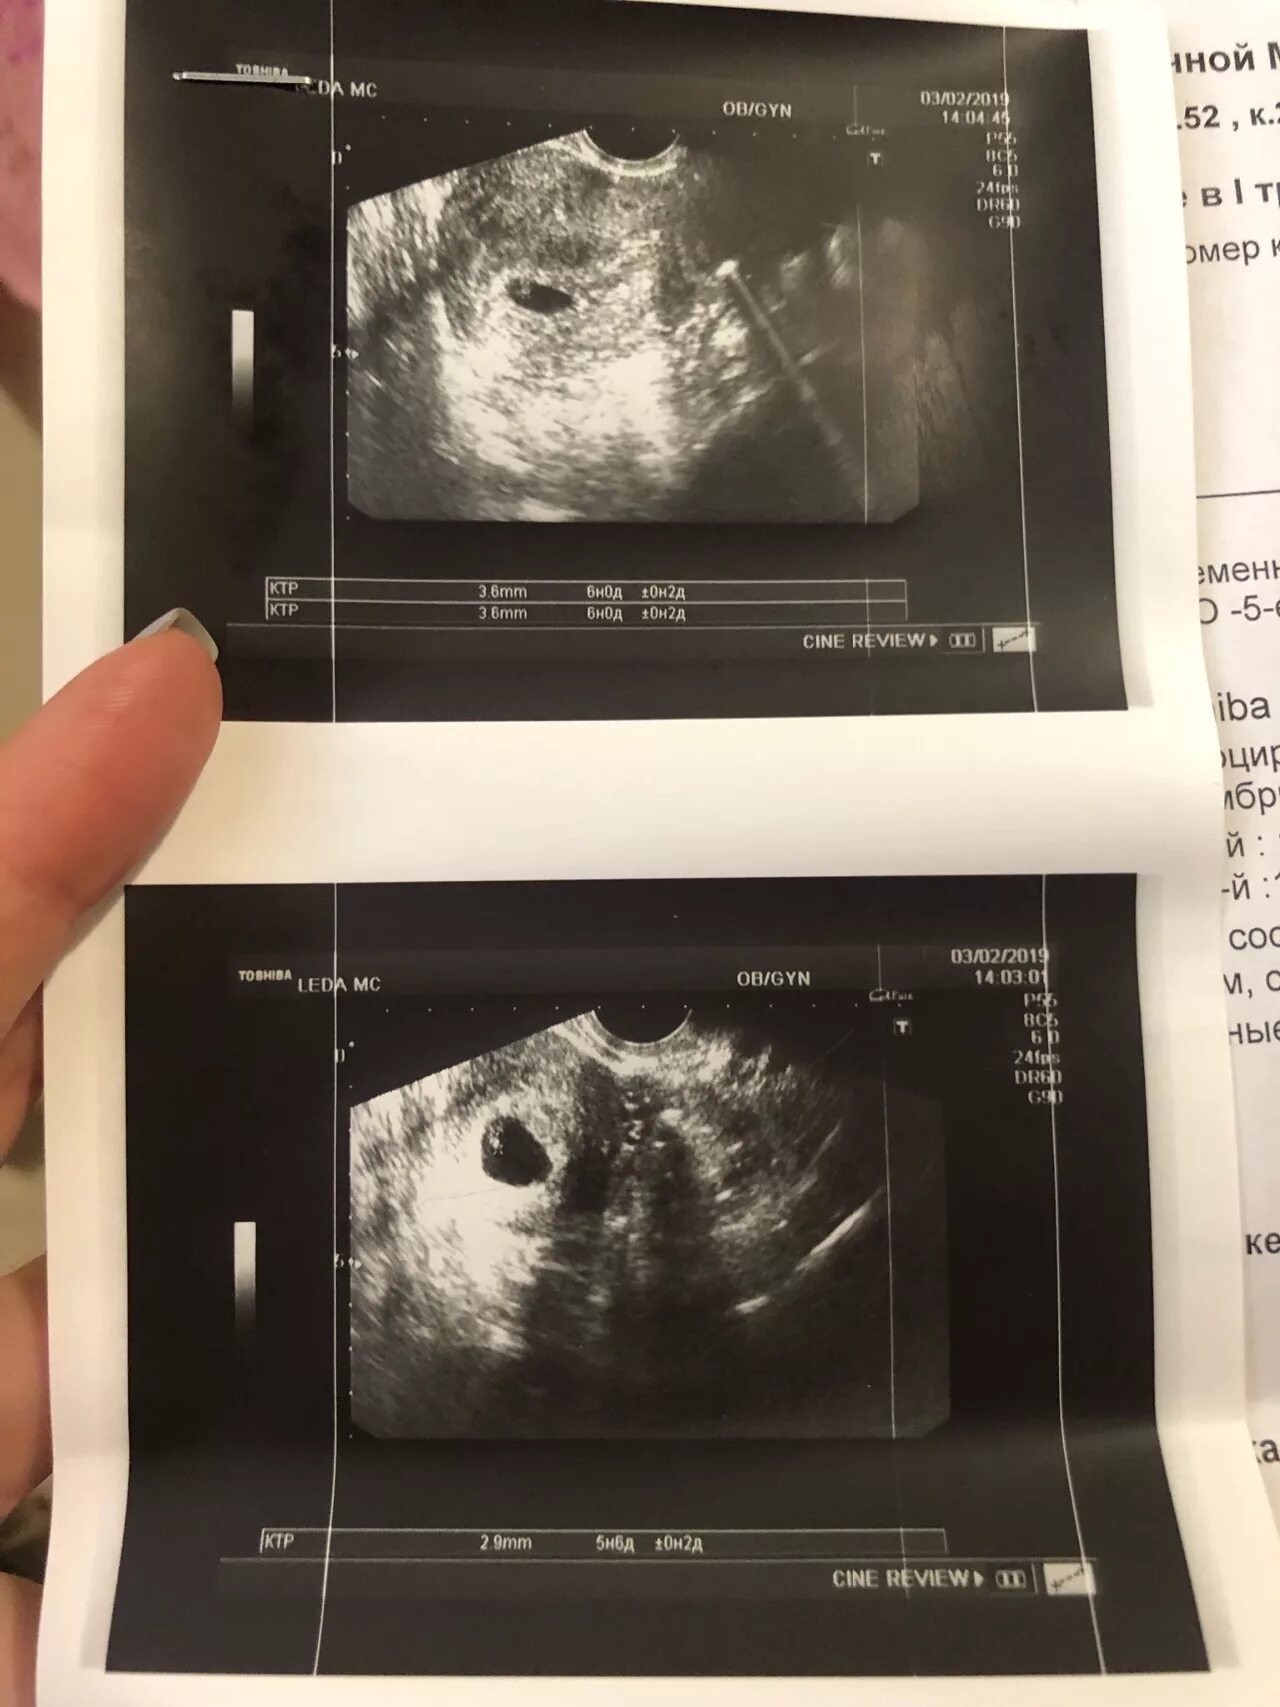

Плодное яйцо желточный мешочек